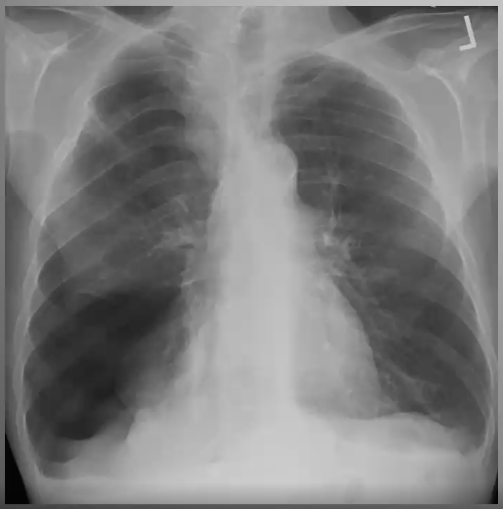

What’s your diagnosis?

Right middle lobe pneumonia because loss of right heart border (silouhette sign)